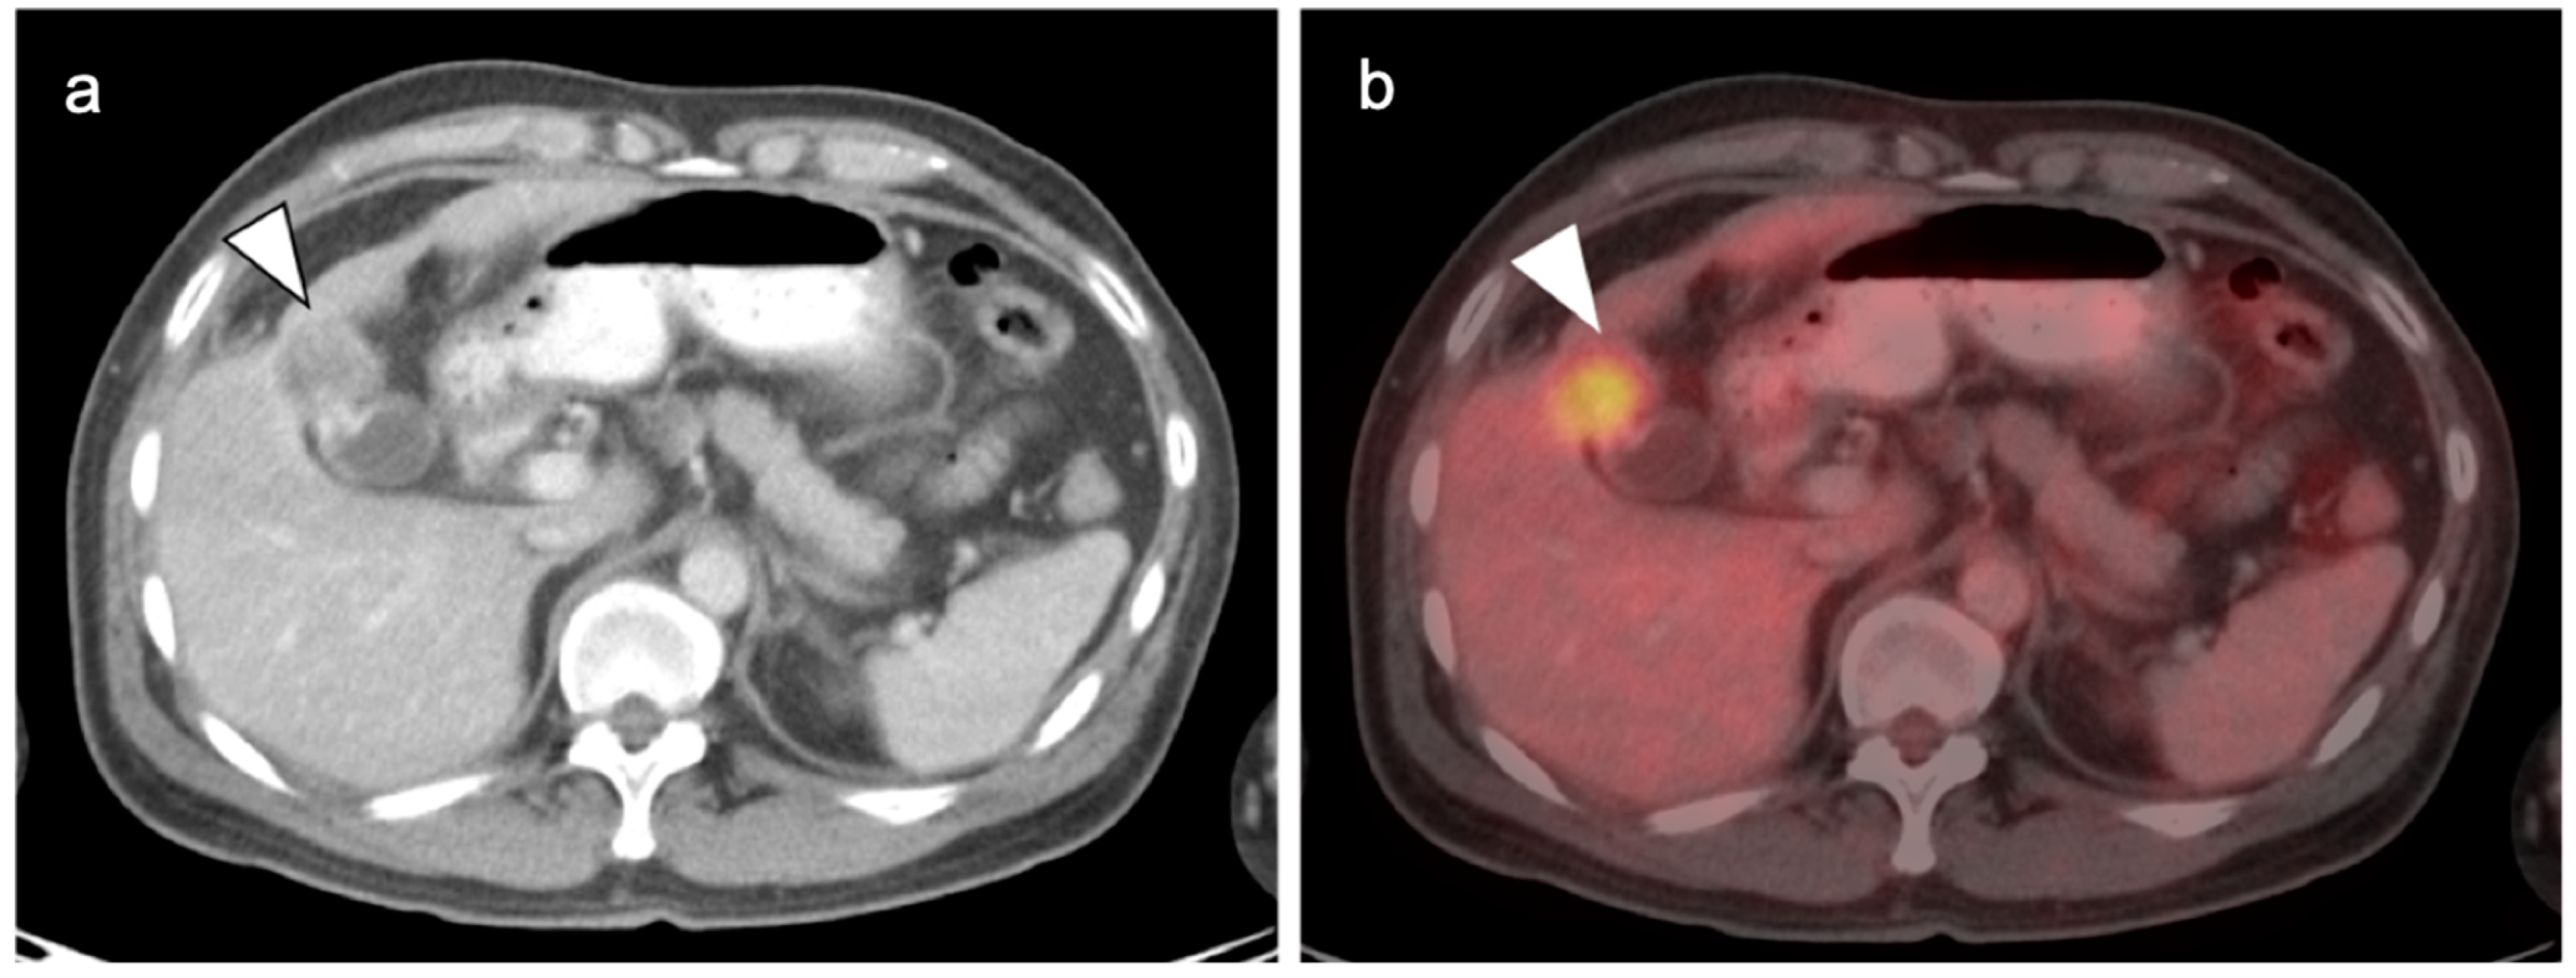

7. Adrenal Cancer

- Dinnes, J.; Bancos, I.; Ferrante Di Ruffano, L.; Chortis, V.; Davenport, C.; Bayliss, S.; Sahdev, A.; Guest, P.; Fassnacht, M.; Deeks, J.; et al. Management of endocrine disease: Imaging for the diagnosis of malignancy in incidentally discovered adrenal masses: A systematic review and meta-analysis. Eur. J. Endocrinol. 2016, 175, R51–R64. [Google Scholar] [CrossRef] [PubMed]

- Okada, M.; Shimono, T.; Komeya, Y.; Ando, R.; Kagawa, Y.; Katsube, T.; Kuwabara, M.; Yagyu, Y.; Kumano, S.; Imaoka, I.; et al. Adrenal masses: The value of additional fluorodeoxyglucose-positron emission tomography/computed tomography (FDG-PET/CT) in differentiating between benign and malignant lesions. Ann. Nucl. Med. 2009, 23, 349–354. [Google Scholar] [CrossRef]

- Vos, E.L.; Grewal, R.K.; Russo, A.E.; Reidy-Lagunes, D.; Untch, B.R.; Gavane, S.C.; Boucai, L.; Geer, E.; Gopalan, A.; Chou, J.F.; et al. Predicting malignancy in patients with adrenal tumors using 18F-FDG-PET/CT SUVmax. J. Surg. Oncol. 2020, 122, 1821–1826. [Google Scholar] [CrossRef]

- Kunikowska, J.; Matyskiel, R.; Toutounchi, S.; Grabowska-Derlatka, L.; Koperski, L.; Krolicki, L. What parameters from 18F-FDG PET/CT are useful in evaluation of adrenal lesions? Eur. J. Nucl. Med. Mol. Imaging 2014, 41, 2273–2280. [Google Scholar] [CrossRef]

- Dong, A.; Cui, Y.; Wang, Y.; Zuo, C.; Bai, Y. 18F-FDG PET/CT of Adrenal Lesions. AJR Am. J. Roentgenol. 2014, 203, 245–252. [Google Scholar] [CrossRef]